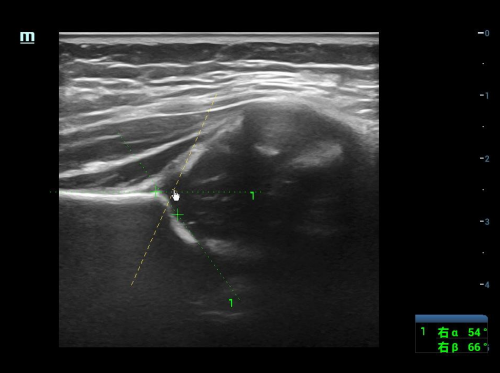

很多家长担心检查会让宝宝不适,对此特检科超声医生表示大可放心。髋关节超声检查全程温和无创,宝宝只无需空腹、憋尿,只需安静配合几分钟即可完成全面筛查,家长可全程陪同;检查时宝宝侧躺、受检侧髋关节朝上,保持髋关节弯曲90度、轻微向内旋转的自然放松姿势,医生会通过超声仪器,找到能清晰看到髂骨下缘、骨性髋臼顶、髋臼盂唇三点的标准切面,再通过两个核心角度判断髋关节发育情况——α角反映髋臼的骨性发育和深度,β角反映软骨的覆盖情况。根据这两个角度,医生会将髋关节发育分为不同类型,对应不同的处理方式。

近期髋关节超声筛查中发现的髋关节发育不良病例